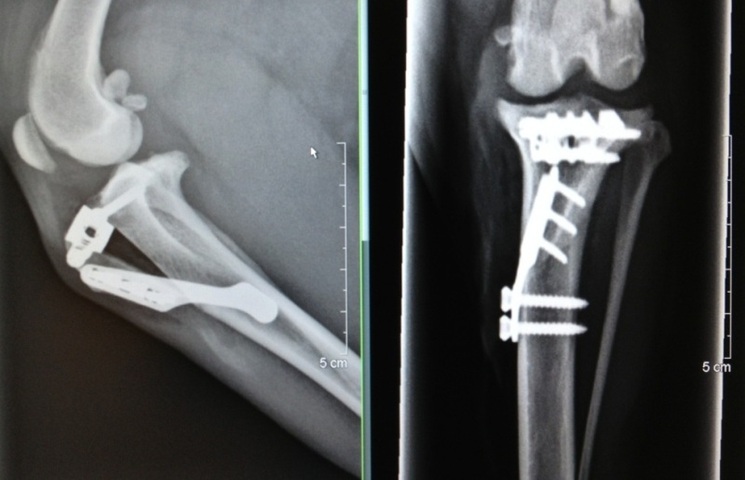

TTA är en modern operationsmetod där benfästet till knäskålens raka band flyttas och fixeras med plattor, distanser och skruvar i titan (se bilden). Resultatet blir en stabilisering av knäleden som ersätter det skadade korsbandet. En stor fördel med operationsmetoden är att den är icke-invasiv, dvs man behöver inte öppna upp knäleden och förhindrar därmed att störning av den känsliga miljön i knäleden. Efter operation är rehabilitering (t ex sjukgymnastik och simning) viktigt för att knäleden ska återgå till normal funktion.